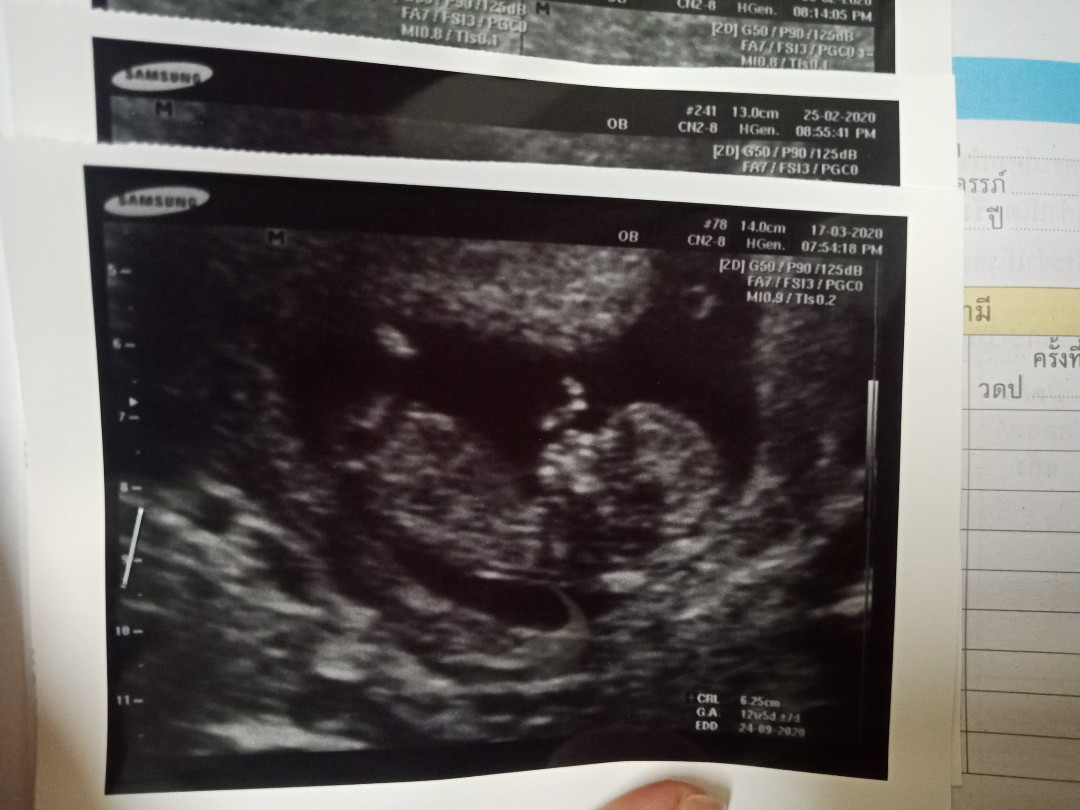

แม่ๆคนไหนมีภาพอัลตร้าซาวด์ประมาณ13วีคบ้างคะ ของเรา13วีค ภาพแบบนี้ค่ะ ดูไม่ออกเลย?

13w ค่ะ